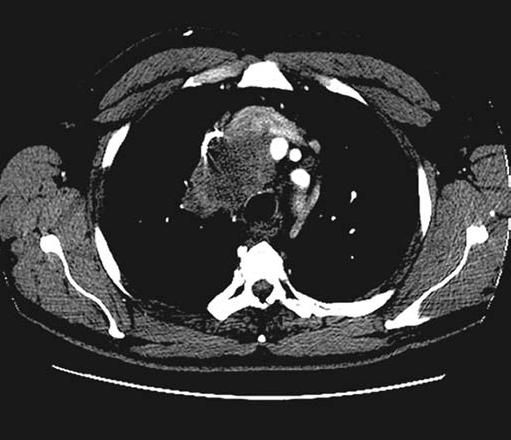

The patient's chest radiograph (Figure 1) and CT scan of the chest after administration of intravenous contrast material (Figure 2) are shown below.

Figure 1 Figure 2

The CT scan of the patient's chest showed a soft tissue attenuation mass in the middle mediastinum, causing marked compression of the superior vena cava (SVC). Tracheal compression and hypodense lesions suggesting malignancy in the left kidney and bilateral adrenal glands were also present.